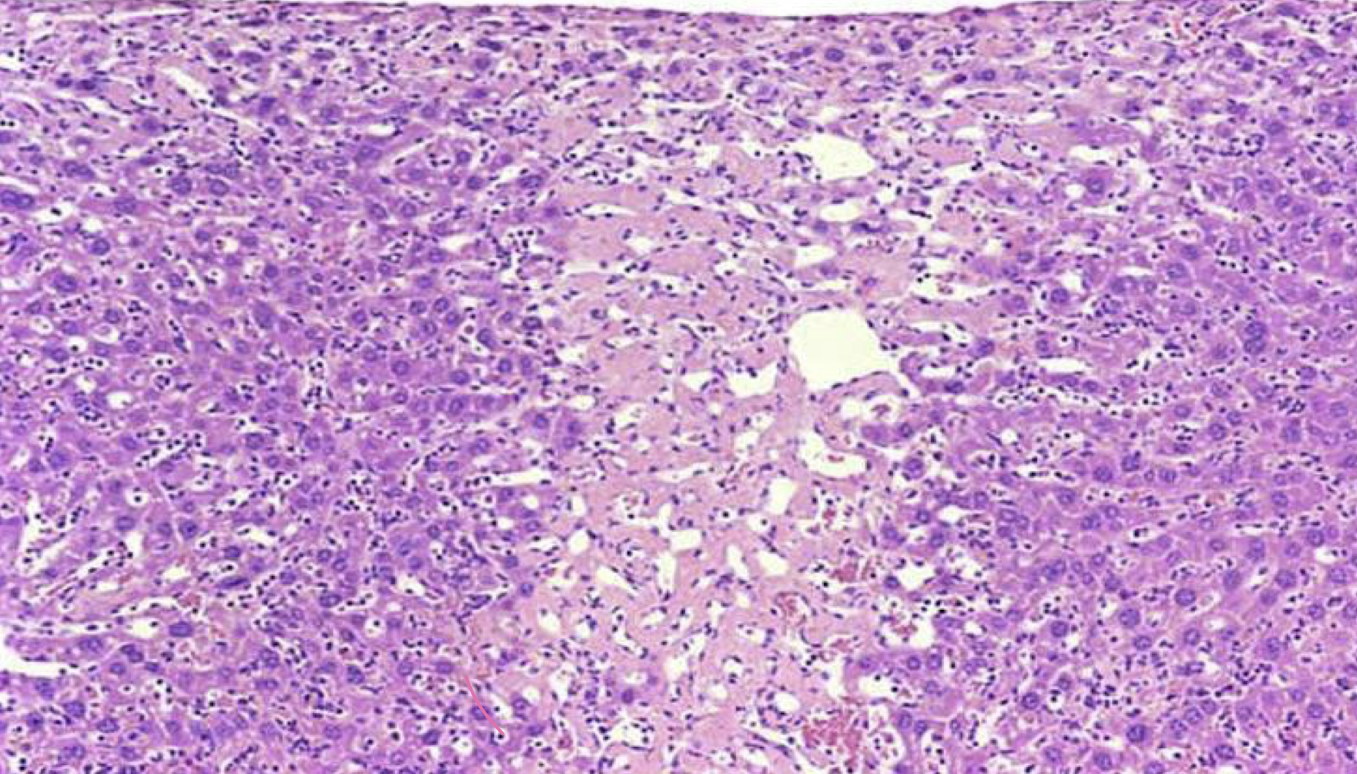

What is this an image of?

necrosis